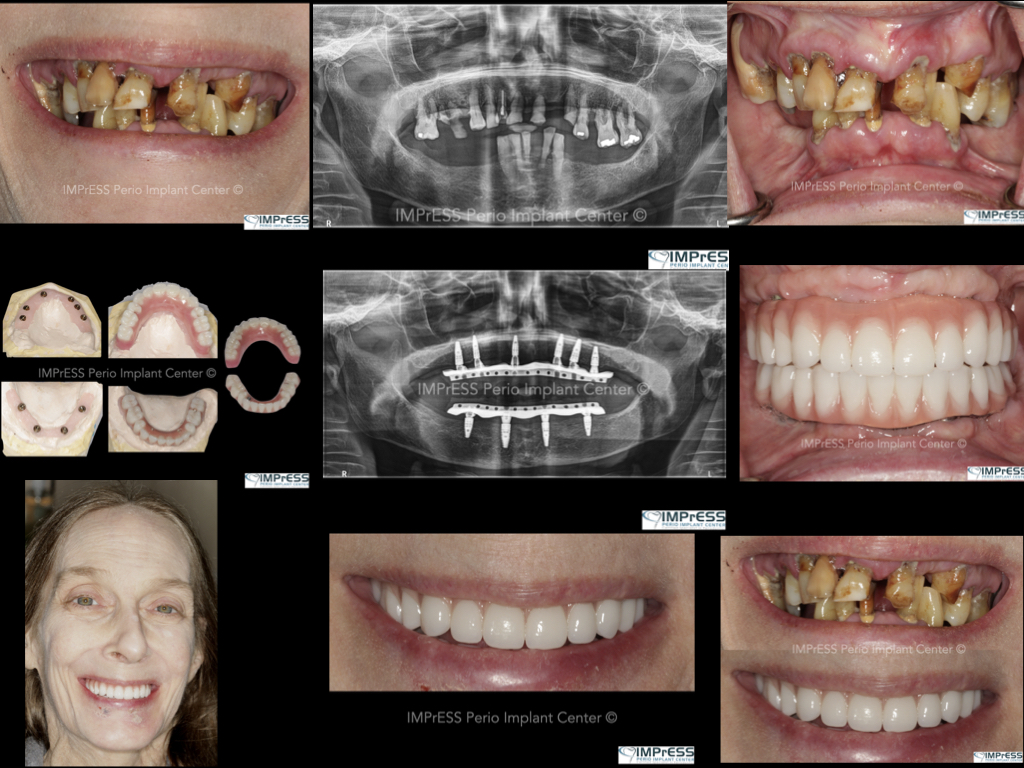

Full Mouth Reconstruction with Fixed Implant Bridge – All on X

All on X implant Full Mouth Implant Reconstruction All on 4 Implants IMPrESS Perio Implant Center Vancouver Burnaby Periodontist Prosthodontist Implant Specialist Dr. Noroozi Periodontist Implant Specialist

mile Makeover with Full Mouth Implants IMPrESS Perio Implant Center Burnaby BC Dr Noroozi

Full Mouth Implant Rehabilitation IMPrESS Perio Implant Center Dr. Noroozi implant Specialist Burnaby Vancouver BC

All On X Full Mouth Implants Fixed Teeth IMPrESS Perio Implant Centre Dr Noroozi Burnaby Vancouver BC

All on X Full Mouth Implant Rehabilitation IMPrESS Perio Implant Center Dr. Noroozi Implant Specialist Burnaby

All on X implant Full Mouth Implant Reconstruction All on 4 Implants IMPrESS Perio Implant Center Vancouver Burnaby Periodontist

Full Mouth Implant Restoration Burnaby Implant Specialist IMPrESS Perio Implant Center Dr. Noroozi

Full Mouth Implants IMPrESS Perio Implant Center Burnaby Vancouver BC Dr. Noroozi All On 4 Implants